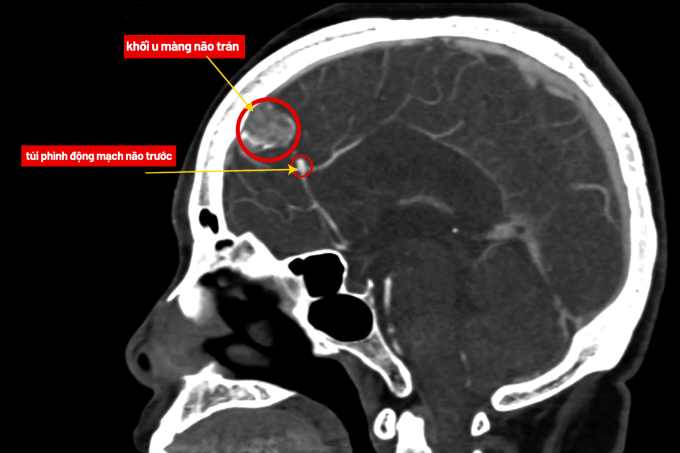

Bà Hiền, 65 tuổi, đau đầu, choáng váng, bác sĩ phát hiện u màng não và túi phình mạch não dọa vỡ, phẫu thuật xử lý triệt để.

TS.BS Nguyễn Đức Anh, Trưởng khoa Ngoại Thần kinh Cột sống, Bệnh viện Đa khoa Tâm Anh Hà Nội, cho biết túi phình của bà Hiền có nguy cơ vỡ gây xuất huyết não. Trong khi đó, u màng não phát triển dễ chèn ép, tạo áp lực lên nhu mô não và hệ thần kinh.